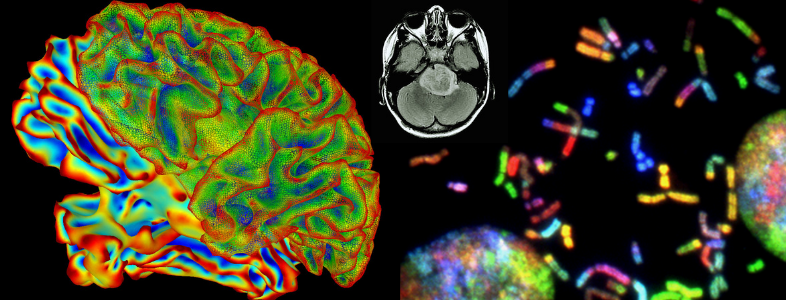

Student David Krist is preparing to play a part in developing revolutionary new treatments for malignant brain tumors – some of the deadliest neurological conditions. Krist is involved in clinical research to analyze a technique that uses fluorescent molecules to clearly differentiate tumors from healthy tissue, resulting in safer surgical removal.

Krist’s clinical research project through Carle Neurosurgery allowed him to observe the technique in action. “I will never forget watching Carle neurosurgeon Dr. Wael Mostafa access and remove a glowing, fluorescein-infused glioblastoma (GBM) brain tumor,” said Krist. With no known cure for GBM, current treatments such as surgical removal are life-lengthening measures. Tumor recurrence following surgery is common.

Krist hopes to help change the paradigm, with research that lays the groundwork toward developing a ‘molecular toolkit’ to fight brain cancer in the future. “I will use this experience along with my previous training in chemical biology to partner with others in advancing the current revolution of molecular and genetic therapies,” said Krist. “Hopefully, we can extend new technology to target glioblastoma and other intractable cancers.”